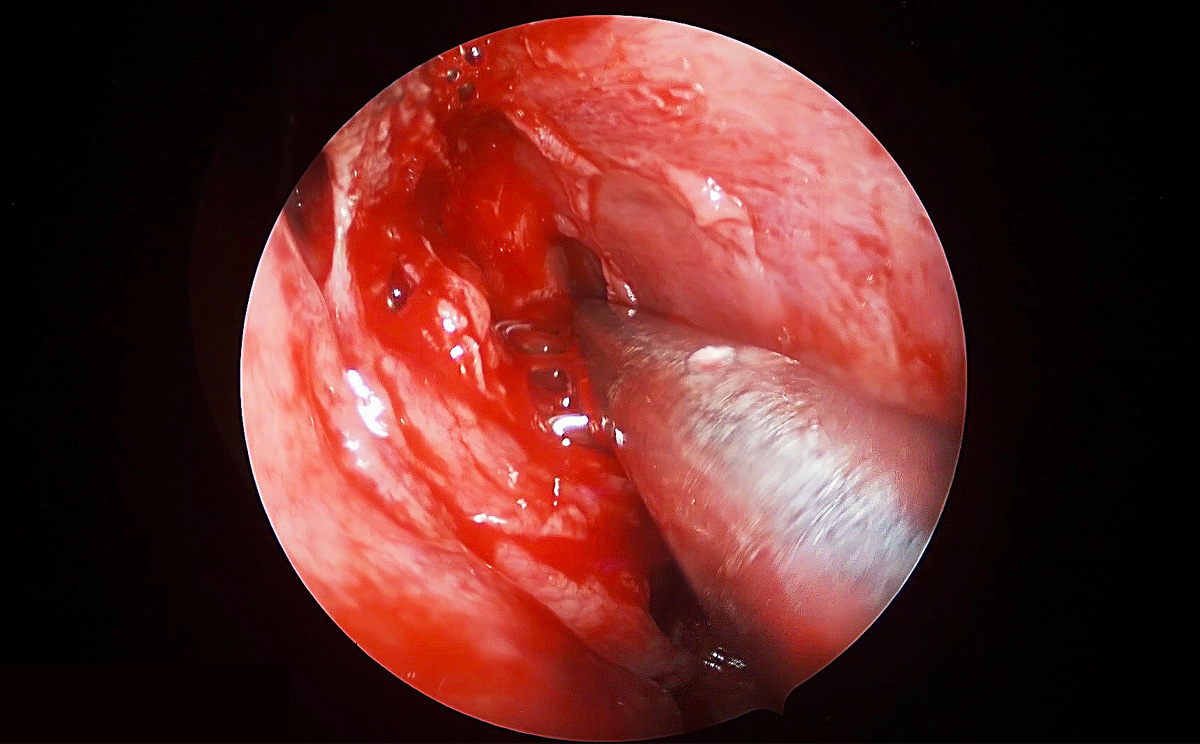

4K超高清內(nèi)窺鏡攝像系統(tǒng)在腦垂體瘤切除術(shù)中的精彩表現(xiàn)

此次手術(shù)采用內(nèi)窺鏡下經(jīng)鼻進(jìn)路行腦垂體瘤切除術(shù),使用機(jī)器益柯達(dá)4K超高清內(nèi)窺鏡攝像系統(tǒng),分辨率可達(dá)3840X2160P,是全高清內(nèi)窺鏡分辨率(1920X1080P)的4倍,該產(chǎn)品具有出色的色彩還原功能,能夠精細(xì)的顯示手術(shù)中的細(xì)微血管、神經(jīng)、筋膜層次,使手術(shù)更精準(zhǔn)、安全。